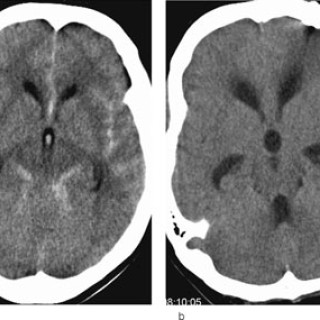

Tema: Hjerneslag